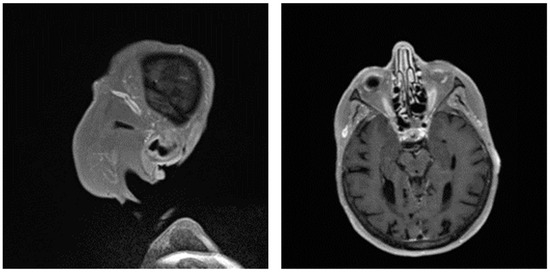

Giant cell arteritis (GCA) affects typically large- and medium-sized arteries, including the carotid arteries and their extracranial branches, as well as the aorta and its branches [48]. Symptoms of GCA include headache, jaw claudication, tenderness of the temporal artery, and low-grade fever [49]. Typical complications of GCA include acute loss of vision and aortic aneurysms, which in turn can lead to more severe complications like stroke or aortic dissection [49,50]. GCA is frequently linked with polymyalgia rheumatica (PMR), characterized by muscle pain and bilateral morning stiffness in the proximal extremities. At a microscopic level, giant cells infiltrate the vascular wall, leading to an occlusion of the affected blood vessels and thus to ischemia of the tissue to be supplied [51]. The diagnosis of PMR/GCA is usually based on clinical presentation, imaging, temporal artery biopsy (Figure 2C,D, Figure 3 and Figure 4), and the ACR/EULAR classification criteria [49,52].

Figure 2. Ultrasonographic findings in patients with large vessel vasculitis: (A,B): B-mode US with the finding of concentric carotid intima-media thickening in a patient with Takayasu’s arteritis ((A) longitudinal plane, (B) transversal plane). (C). B-mode US: carotid intima-media thickening in a patient with giant cell arteritis. (D): Power Doppler US in a patient with temporal arteritis (typical “HALO” sign). Courtesy of Dr. Konstantinos Triantafyllias, Rheumatology Center, Rhineland-Palatinate.